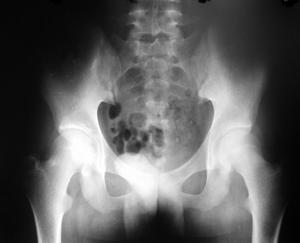

2.受累關節及胸部X線攝片、心電圖檢查。 必要時行超聲心動圖檢查。

①每日關節晨僵至少1h(≥6周);②3個或3個以上關節腫(≥6,周);③腕、掌指關節或近端指間關節腫(≥6周);④對稱性關節腫(≥6周);⑤皮下結節;⑥手X線片改變;⑦類風濕因子陽性(滴度>1∶32)。具備4條或4條以上標準,可確診。